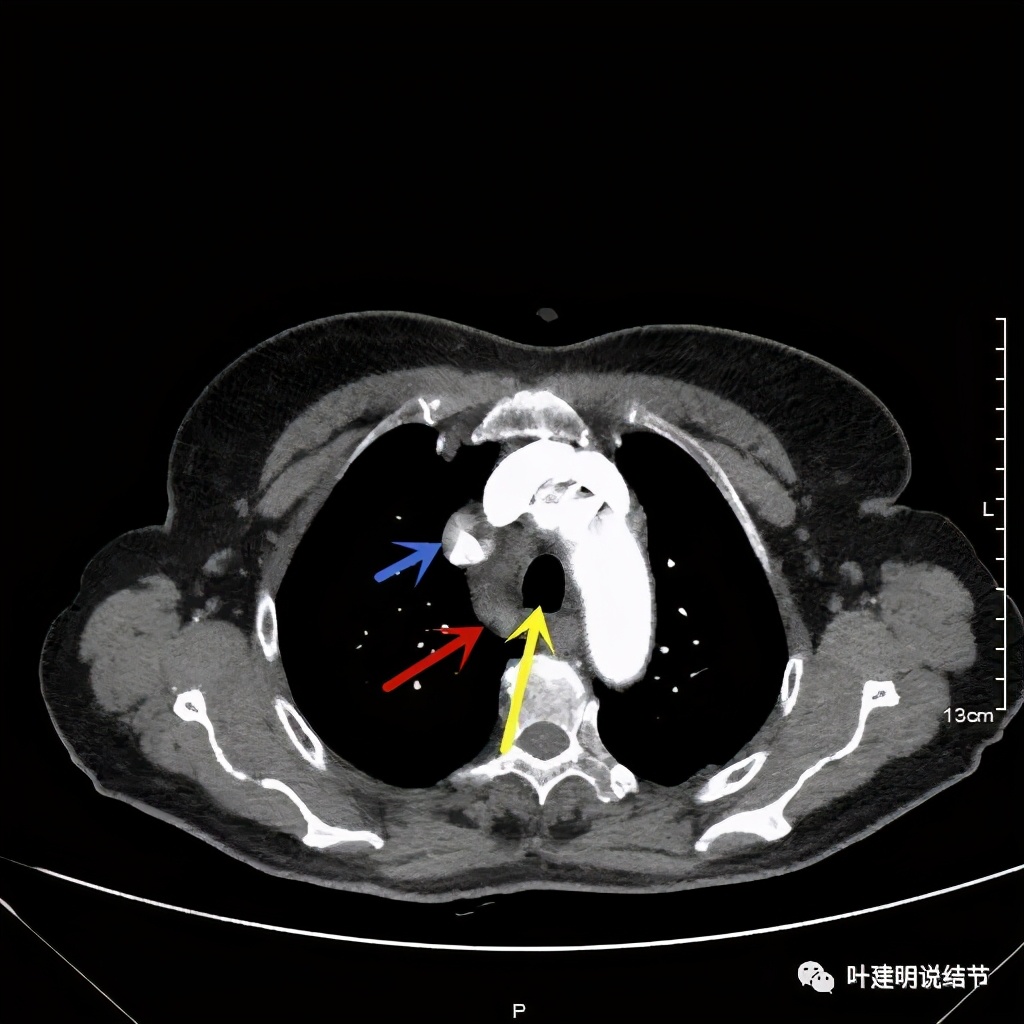

上图红色示肿瘤,黄色示气管,粉色示肿瘤与气管关系密切,桔色示左无名静脉,肿瘤密度不均